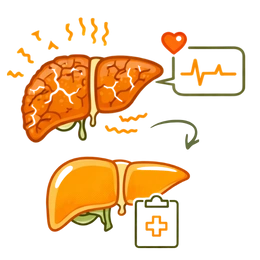

What is Fatty Liver Disease? (Hepatic Steatosis) & its Types

Fatty liver disease (hepatic steatosis) is a condition characterized by the buildup of too much fat inside liver cells. Our liver can have a little fat normally. It is when the fat is more than 5% to 10% of the liver weight that it is treated as a problem requiring a doctor’s intervention. Therefore, a person needs to be identified at the initial stage in order to have a good fatty liver therapy.

Fatty liver stages (reversibility):

- Grade 1 (Simple Fatty Liver):Presence of fat accumulation without inflammation. Very much reversible through diet and Ayurvedic medication.

- Grade 2 (Moderate):Higher fat content with a slight inflammatory state. Hence, the only condition that can be reversed with strict care and giving up bad habits.

- Grade 3 (Severe/Fibrosis):Where the inflammatory reaction is accompanied by tissue damage. Therefore, it is hard to reverse but the condition can be controlled through a good liver detox.

- Cirrhosis: It is the last stage where the liver has been extensively scarred and totally lost the ability to function.